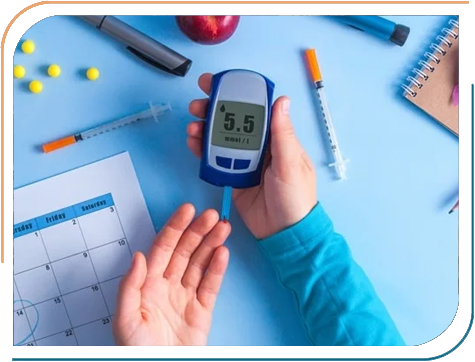

Dr. Jhala's expertise encompasses a wide range of paediatric endocrine disorders, including Growth abnormalities, Childhood Diabetes, Thyroid disorders in Children, Puberty-related concerns, Bone diseases and many other hormonal conditions in Children. She is dedicated to diagnosing and treating conditions such as Type 1 diabetes, Growth hormone deficiencies, and early or delayed puberty, all aimed at helping children lead healthier, more fulfilling lives. Her approach combines thorough clinical evaluation with the latest medical advancements, ensuring comprehensive care tailored to each child's needs.